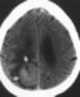

Central nervous system anomaly